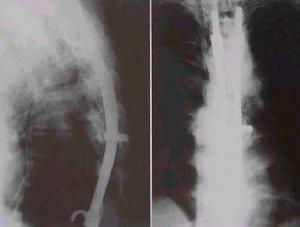

(1)椎旁膿腫引流術化膿性脊椎炎,經椎旁穿刺抽得有膿液或CT掃描顯示有椎旁有膿腫者,應及時行膿腫切開引流,以控制病變發展,減輕全身中毒症狀。

脊椎骨骨髓炎--治療(2)椎板切除硬膜外膿腫引流術急性化膿性脊椎炎,一旦出現脊髓壓迫症狀,如下肢無力,感覺改變或尿瀦留等症狀,應緊急行CT掃描檢查。如顯示為硬膜外有膿腫壓迫脊髓時,立即行椎板切除、硬膜外膿腫引流,以防止截癱加重,或脊髓營養血管栓塞、脊髓軟化、壞死等。術後常放管負壓引流,或置管行沖洗吸引療法。待體溫正常、症狀好轉,引流液清淨後拔除。